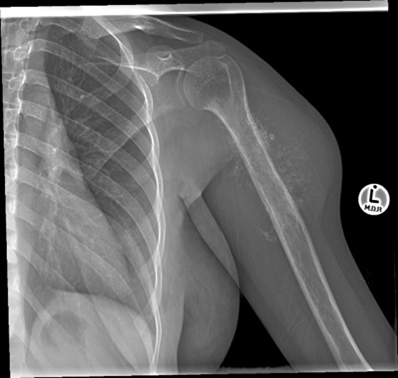

Osteosarcoma. There are many types of osteosarcoma but the most common is the classic intramedullary type which usually originates from the intramedullary cavity of the metaphyseal area of long bones. It is the most common type of bone sarcoma overall. It is most often found in teenagers and young adults. Any pathological fracture in a young person must be considered malignant until proven otherwise. The treatment of an osteosarcoma is classically neoadjuvant chemotherapy – surgery – adjuvant chemotherapy. The biopsy to diagnose bone sarcomas should be done by a sarcoma specialist to prevent difficulties with future surgery and spread of the tumour locally. The 5-year survival for patients with osteosarcoma is between 60% and 70%.